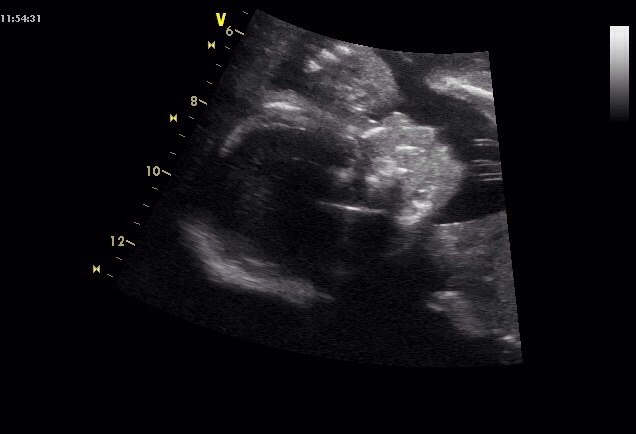

Hezké ráno -) včera jsme byli na screeningu a čekáme chlapečka .jsem 20+4 a prcek je prý podle tabulek 348g a krásně fotky jsme dostali .Prikladam